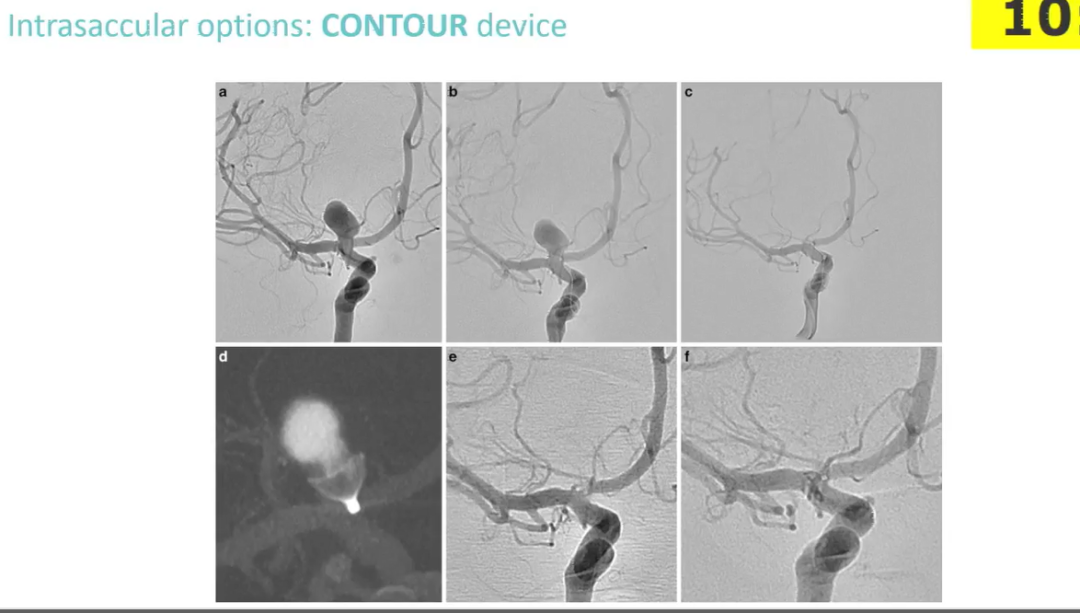

病例展示:

病例一:

首例使用Contour装置治疗的颅内动脉瘤,术中CT可以清晰显示Contour装置的标记点及“篮状”结构,术后随访效果好。

病例二:

Jens Fiehler教授的病例,形态不规则的基底动脉尖动脉瘤,瘤颈4.2mm,最大径5.7mm,根据Contour尺寸推荐,选择9号装置,通过Asahi18微导丝配合Headway27微导管进行释放,术后即刻可以看到造影剂滞留。

术中CT显示Contour装置形态良好,但尾端标记点造成的金属尾影较多,所以无法使用MR进行随访,这是需要持续改进的地方。

术后6个月DSA随访,动脉瘤未治愈,瘤颈有少量残留;但由于金属尾影的干扰,在MRA上动脉瘤及左侧P1均未显影。